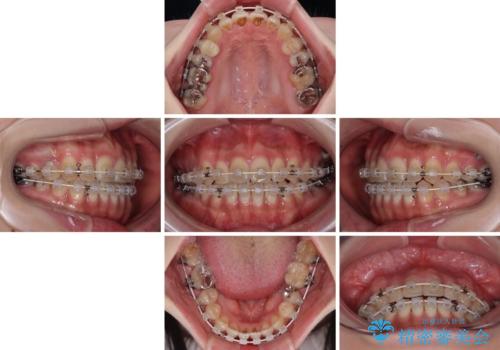

- 矯正装置

- 審美装置

- 治療期間

- 10ヶ月

開咬の方は、インビザライン矯正治療が適していますが、自己管理の煩わしさと、転勤の可能性がありマウスピース矯正であると通院しなくなるだろうとのことで、ワイヤー装置にて矯正治療を行うこととしました。

治療開始から8ヶ月ほどで遠方への転勤が決まりましたが、歯列は概ね整っていたため、その後は東京出張を狙って治療を終える処置を行うことができました。